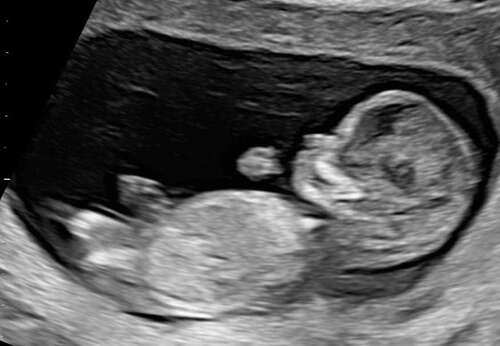

Wowww, richtig groß oder❤️ süßes Profil

Vielen Dank. Für die Woche war er genau richtig. Hat auch ordentlich geturnt.